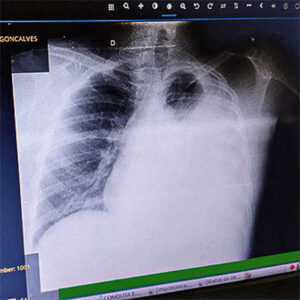

Imagem de capa - Um tipo raro de tuberculose quase o levou a óbito

Ele voltou ao médico, fez vários exames e foi constatado que ele estava com derrame pleural (veja quadro ao lado). “Seis litros de líquido foram retirados de dentro do meu peito, mas era gerado novamente. Os exames laboratoriais davam resultado normal e os médicos não sabiam exatamente o que eu tinha. Eu ainda tive que voltar várias vezes ao hospital para que tirassem o líquido em excesso”, relata.

Por não saber a causa de seu problema, ele se sentia angustiado com a gravidade da situação. “Fiz vários exames até que consegui fazer uma biópsia que apontou que eu tinha tuberculose na pleura, que é mais rara até do que a tuberculose normal, a pulmonar. Por se instalar na pleura, a tuberculose que eu tive agravou o derrame pleural e o inchaço também estava pressionando o meu coração. Como já tinha passado muito tempo, mais de 90% do pulmão esquerdo estava comprometido e eu estava realmente com uma doença rara que poderia me matar”, diz.